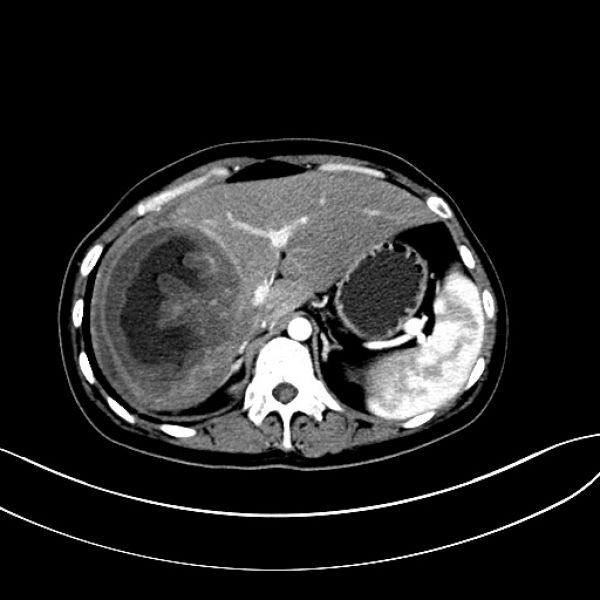

患者转入ICU治疗3天病情稳定后转湘雅医院继续治疗,并再次行肝创面压迫止血棉垫取出术,经积极治疗,患者恢复良好。治疗过程中两次行彩超引导下肝脓肿穿刺引流术,术后病情平稳,恢复出院。患者出院后,因肝脓肿反复住院数次进行脓肿冲洗引流,给患者生理和心理带来了很大影响。8月10患者以“肝脓肿穿刺引流术后3月余”来肝胆一科住院复查治疗,完善肝胆脾CT检查后发现,患者右肝脓肿仍然明显。王文儿主任组织肝胆一科医师进行科内讨论研究指出,通过仔细研究CT片及结合分析患者抢救治疗经过后认为要根治性解决患者目前病灶,必须行右半肝切除。经过与患者家属沟通,仔细说明患者目前病灶情况及治疗方案的利弊之后,家属充分了解并同意手术方案。经过充分术前准备后,于8月14日在全面插管下行右半肝切除+右隔下脓肿清除引流术,术后经积极治疗,患者顺利康复出院。

术后复查CT图像